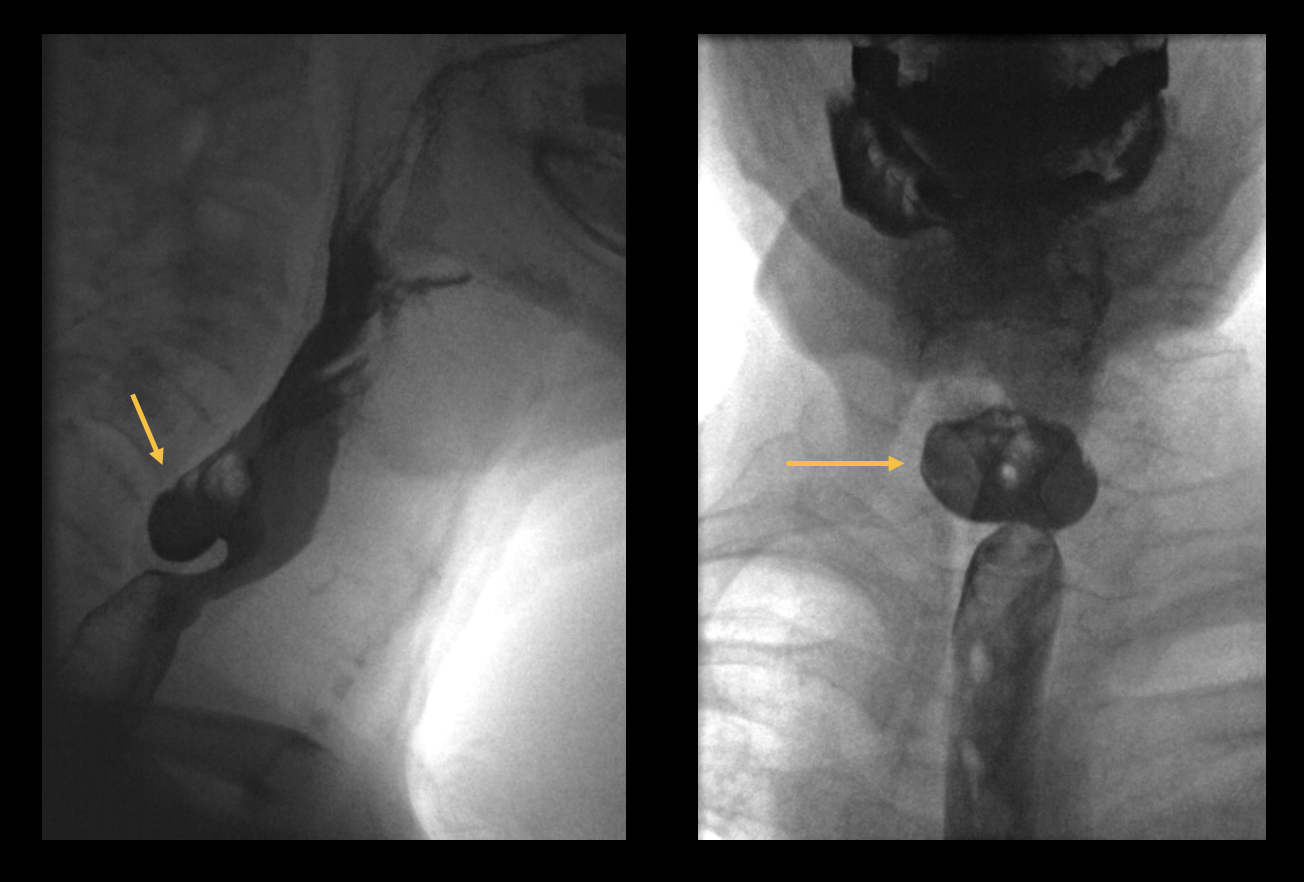

Le difficoltà di deglutizione sono relativamente comuni in età avanzata. Possono essere autolimitanti, ma possono anche durare a lungo. Se i sintomi persistono a lungo, è necessario eseguire una gastroscopia. Se questa non rivela nulla, può essere utile anche un test della deglutizione. Il paziente di 65 anni (vedi illustrazione), ad esempio, presenta un reperto raro: un diverticolo di Zenker.

image1.png

Figura 1: Ipofaringo-esofagografia con mezzo di contrasto contenente bario in vista sagittale e coronale. Si nota una protrusione dorsale della parete esofagea posteriore a livello di C5-C6.